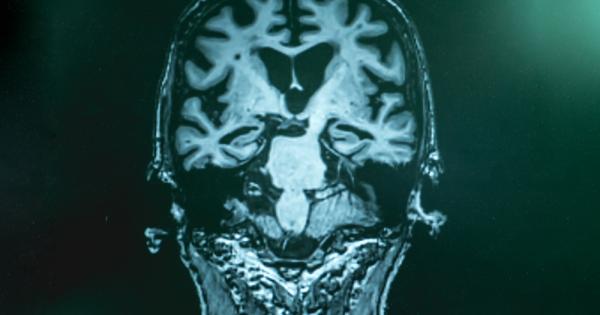

...... разрушава паметта, мисловните умения и в крайна сметка - способността за изпълнение на прости задачи. Конкретните причини за болестта все още не са напълно известни.

...... характеризира с промени в мозъка - включително образуване на амилоидни бета плаки и неврофибриларни заплитания, които водят до загуба на неврони и техните връзки. /БГНЕС

...... плаки (необичайни съсиреци в мозъка на хората с Алцхаймер), които могат да увредят клетките и да предизвикат деменция, включително проблеми с паметта, мисленето и общуването,

...... причина за него. Смята се, че болестта на Алцхаймер, най-честата форма на деменция, засяга 50 милиона души по света и обикновено започва след 65-годишна възраст.